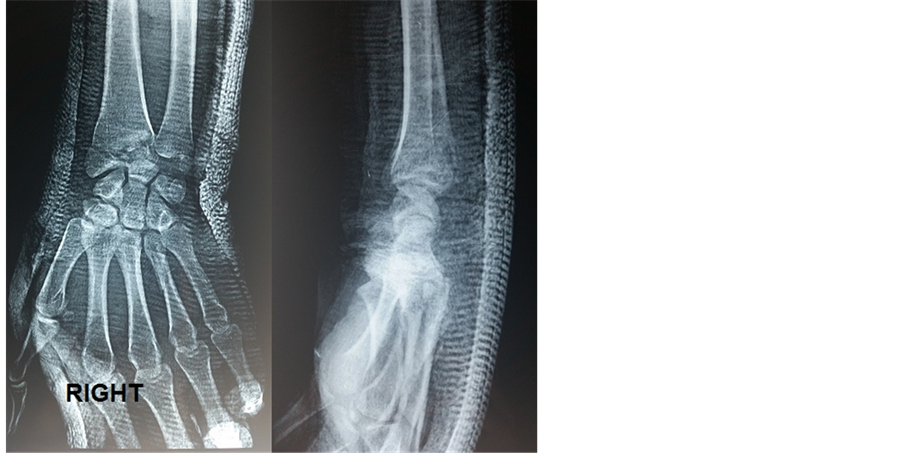

This is a male, 35 year-old patient, builder, without any remarkable medical history who fell from a high place and applied an excessive load to his wrists, which were in extension. He had deformity of both wrists, severe pain and functional disability. Associated to severe pain and functional disability of the right elbow. The initial physical exam found a “dinner fork” deformity in both wrists, increased temperature, severe pain and functional disability. Deformity of the right elbow with ecchymosis. Antero-posterior and lateral wrist X-rays of the wrists and right elbow were taken, which showed dorsal radiocarpal dislocation and fracture of the radial and ulnar styloid process in both wrists (Figure 1 and Figure 2). Dislocation of the right elbow with complex fracture of the radial head and ulnar shaft of the same right upper limb (Figure 3).

In the operating room, Under balanced general anesthesia, closed reduction with external maneuvers were made for both wrists dislocations. Controlled by fluoroscopy, The local temperature and color conditions improved and then an orthopedic treatment was made with cast immobilization for both wrists seeing the stability of the reduction (Figure 4 and Figure 5). Surgical treatment of the elbow before reduction of its dislocation with mini plate for the radial head and a plate of the ulnar shaft (Figure 6).

Figure 4. Right wrist after treatment.

Figure 5. Left wrist after treatment.